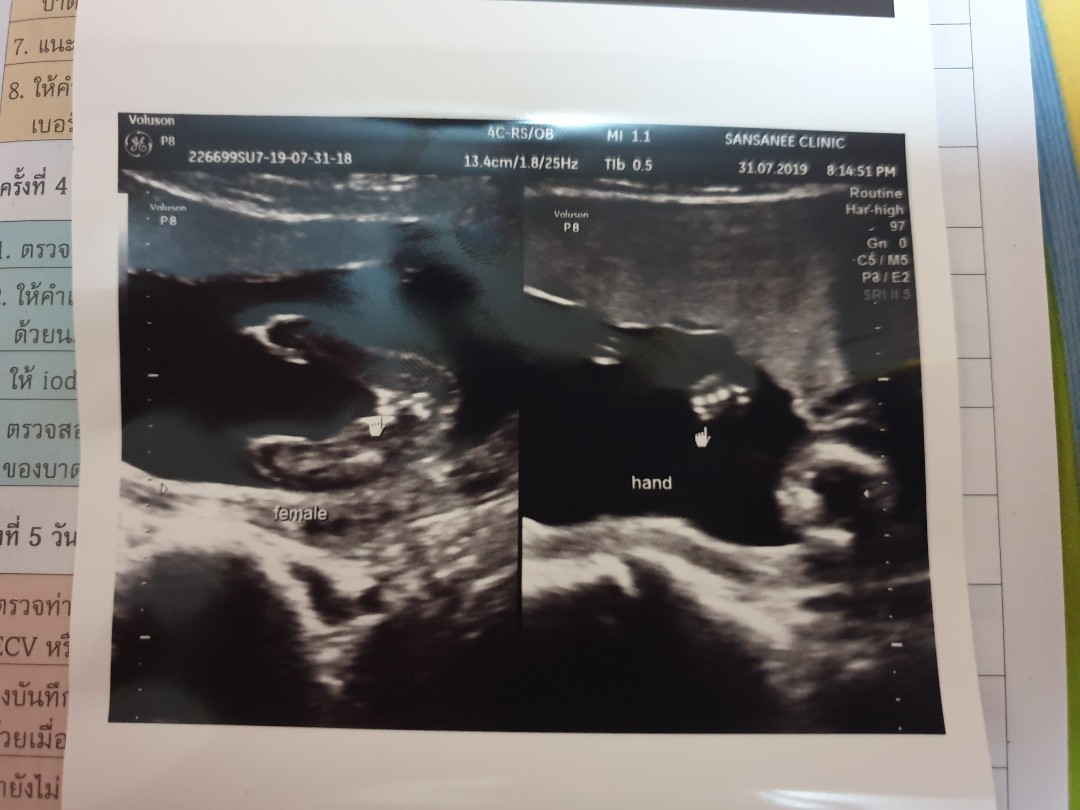

4 เดือน 1 สัปดาห์จ้า น้อง ผญ คะ

ภาพซาวด์ 4เดือนครึ่งคะ ผญ.